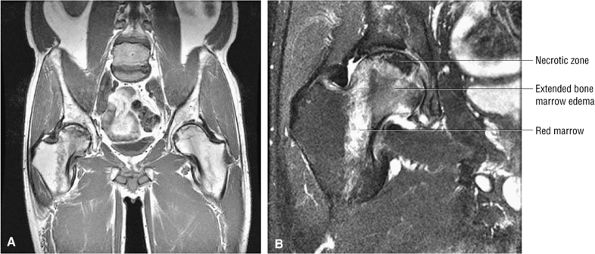

FIGURE 3.87 ● Osteonecrosis with adjacent column of red marrow. Red or hematopoietic marrow should not be mistaken for an extended edema pattern, which is partially shown in the medial femoral head/neck junction. (A) Coronal T1-weighted image, (B) Coronal FS PD FSE image.